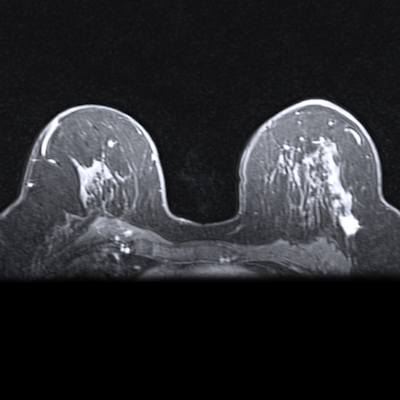

Some breast lesions do not meet the threshold for being classified as a mass. These are defined as nonmass-like lesions, which are areas of altered echotexture that differ from the surrounding breast tissue and do not conform to a mass shape. Differentiating between benign and malignant lesions in this area is important since various breast diseases can present as nonmass-like lesions.

The Niu team wanted to investigate the added value of MRI in assessing nonmass-like lesions detected initially on ultrasound. It also wanted to establish an integrated strategy of ultrasound combined with MRI to improve the diagnostic accuracy of nonmass-like breast lesions.